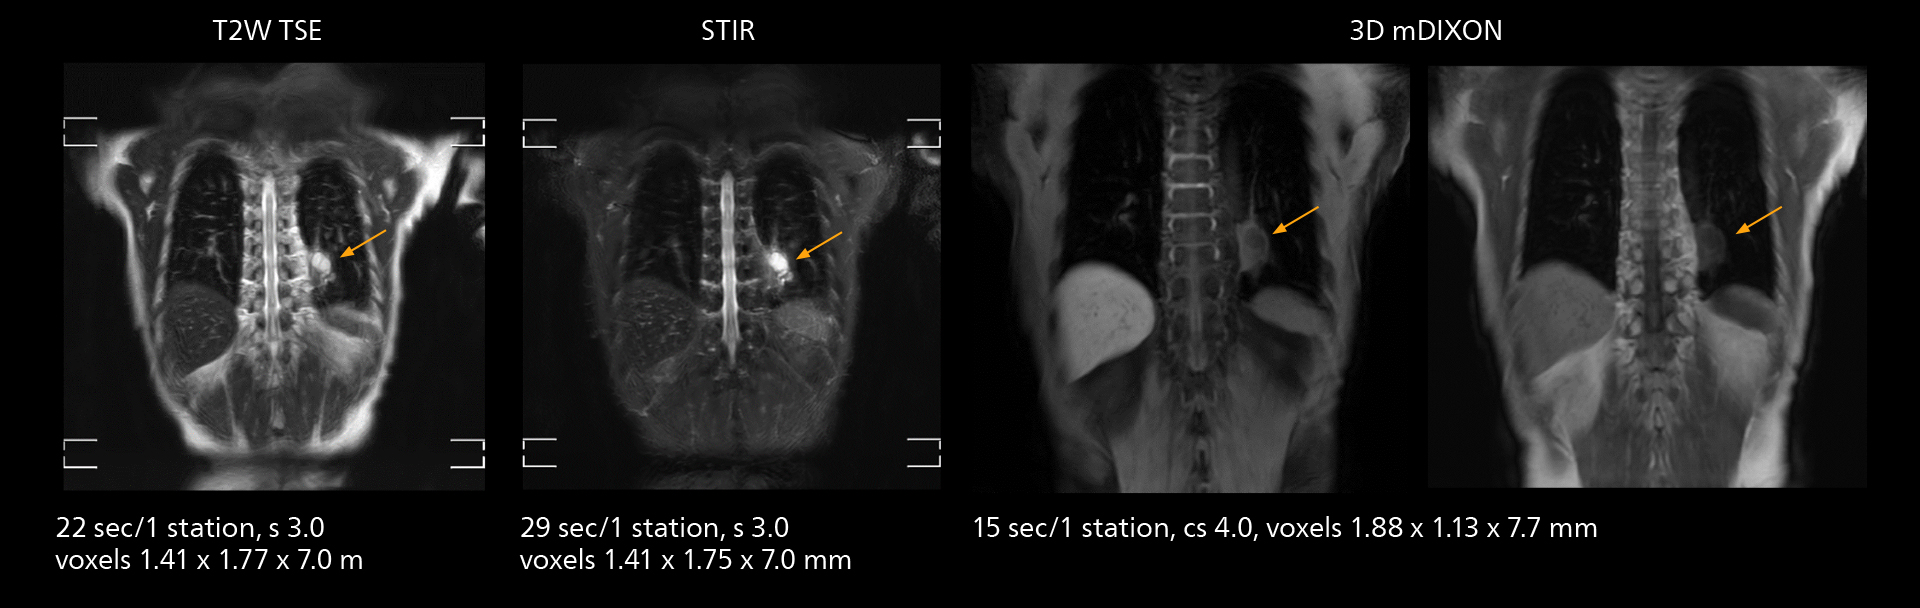

The value of the Elition X gradients is also evident in DWIBS studies. “The fact that we can consistently obtain distortion‐free DWIBS while reducing imaging time at three coronal stations is excellent,” Dr. Makuuchi says. “In these patients, it’s also important that the application of Compressed SENSE to T2‐weighted, STIR and mDIXON sequences has no impact on the examination time of whole‐body imaging. As a result of the increased speed and higher image quality we realize, DWIBS studies have now become routine examinations.”

With SmartPath to Elition X the team can obtain excellent quality DWIBS imaging and reduce imaging time. Other sequences also fit in the examination slot. This case shows left paravertebral neurogenic tumor and Th10 vertebral hemangiomas.